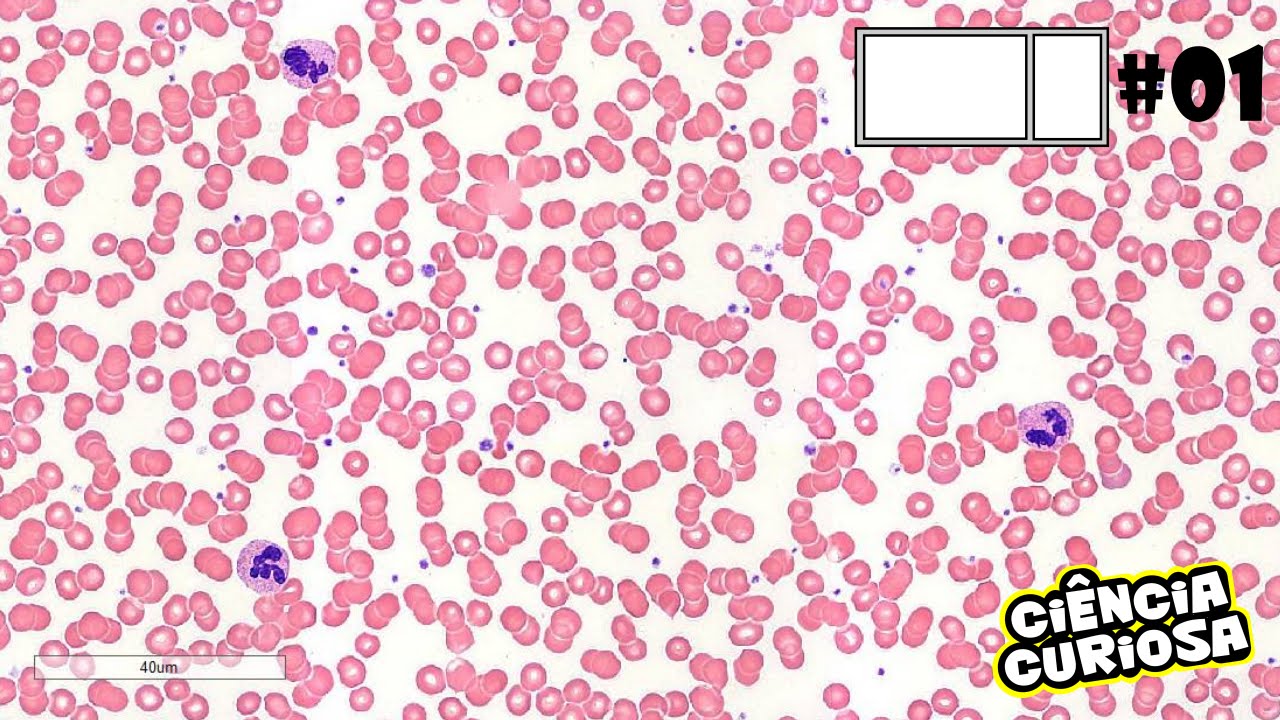

que compõem esse sangue que é o o que começando com a e masha os nossos glóbulos vermelhos que a gente tem que saber sobre masha primeiro era uma célula e será anucleada portanto ela não tem núcleo ela tem um formato meio diferente como a gente vê nessa imagem ela meio é puxada para dentro você sempre pode dizer que a gente chama isso de biconcavo isso é importantíssimo para essa célula que possui só 7.5 micrômetros como a gente veio aqui que essa importância dela ser pequena e bicôncava EA nuclear é exatamente essa flexibilidade que ela vai

ter o que essa flexibilidade é importante Principalmente quando ela passar por capilares muito pequenos onde ela consegue certa deformidade para passar por esses locais muito estreitos não lembro ela é sem núcleo e é o bico que facilita essa flexibilidade dessa célula Outro ponto ela possui a hemoglobina dentro dela essa hemoglobina que estaria associada o ferro e estaria Transportando o famoso oxigênio para as nossas células Então lembre-se dentro dessa massa tem hemoglobina conjugada com ferro para transportar o oxigênio Lembrando que a principal fonte de energia dessas células seria ver quase e ela tem uma duração no

imaturas B o início eu só quero que você guarde isso a gente vai aprofundar isso mais à frente agora outro ponto é que a lista acaba diferenciando uma hemácia normal de um reticulócito é que ela não pense formato ali completamente bicôncavo e possui ribossomos dentro dele como a gente mesmo essa imagem vários pontinhos ali e característica a presença desse robô sol bela a gente já falou das hemácias os reticulócitos que são é massas e matures e os leucócitos galera os leucócitos eles são produzidos também na medula óssea mas também nos órgãos linfoides eles são temporários

no sangue ele só atuou em um momento que eu necessito de ação de defesa no nosso corpo é ou seja eles sofrem a diapedese eles migram para os tecidos-alvo onde está tendo algum problema para eles combater esses agentes o vírus bactérias etc Beleza então eu posso só agem ou seja estão presentes no sangue quando tem algum probleminha tranquilo são produzidos na medula óssea e também em órgãos linfoides a gente pode dirigir destacar e diferenciar esses linfócitos são classificados em agranulócitos e granulócitos os granulócitos galera seriam neutrófilos eosinófilos e os basófilos já quando a gente fala

dos agranulócitos seriam linfócitos e monócitos vamos falar primeiro sobre os granulócitos começando com o neutrófilo o meu troco galera é uma célula arredondada seria grande e ela é segmentada a construir ele alguns Logos que a gente vê aqui nessa imagem esses esses neutrófilos possui até 5 Logos o possui os gregos principalmente grânulos azurófilos e específicos a principal função dessa célula galera seria na fagocitose e Destruição além das bactérias e também de alguns agentes invasores e não são desejáveis nesse organismo então eles vão fagocitar e destruir bactérias outro leucócito que é granulócitos eosinófilos esse osinox também